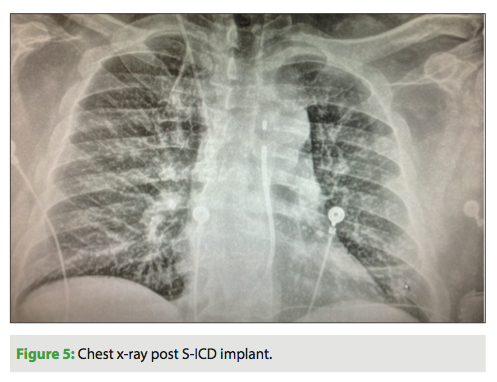

Another advantage of the S-ICD in these situations is that whereas it is normally recommended to wait two weeks prior to re-implantation, the S-ICD does not require this two-week wait. I prefer not to combine the two procedures due to the vastly different preparation areas and procedures. Instead, we bring the patients back the following day for S-ICD implantation. Figure 5 shows the result after S-ICD implant.